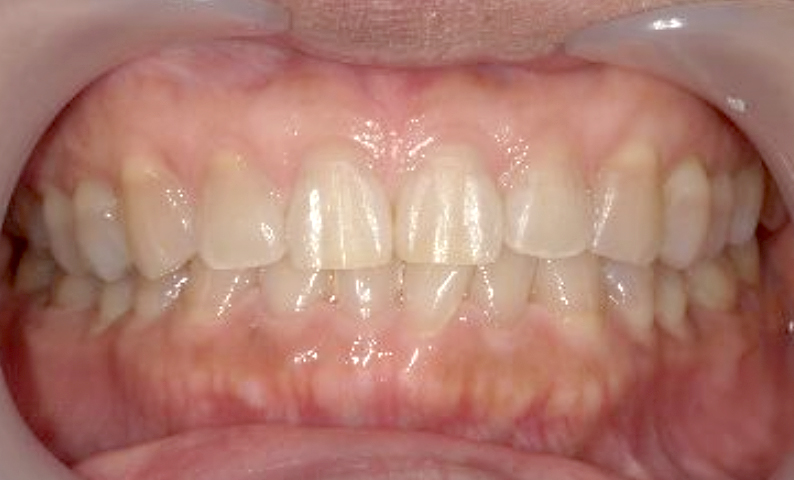

| 治療前 | 治療後 |

|---|---|

|